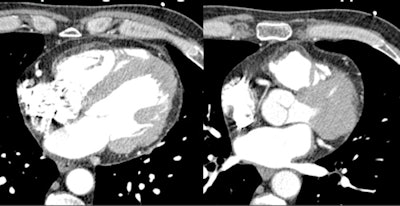

Arrythmogenic right ventricular dysplasia at CT. All images courtesy of Dr. Hans-Christoph Becker.Dilated cardiomyopathies

Patient scheduled for aortic valve replacement was found to have significant calcification in the myocardium of unknown etiology.Another incidental finding occurred in a patient being readied for a transcatheter aortic valve replacement (TAVR). However, instead of aortic disease he was found to have hypertrophic obstructive cardiomyopathy. CT is very helpful because this disease requires a very morphologic diagnosis, in this case showing a mass of soft tissue in the myocardium in the territory of the aortic outflow track as an indicator of hypertrophic obstructive cardiomyopathy.